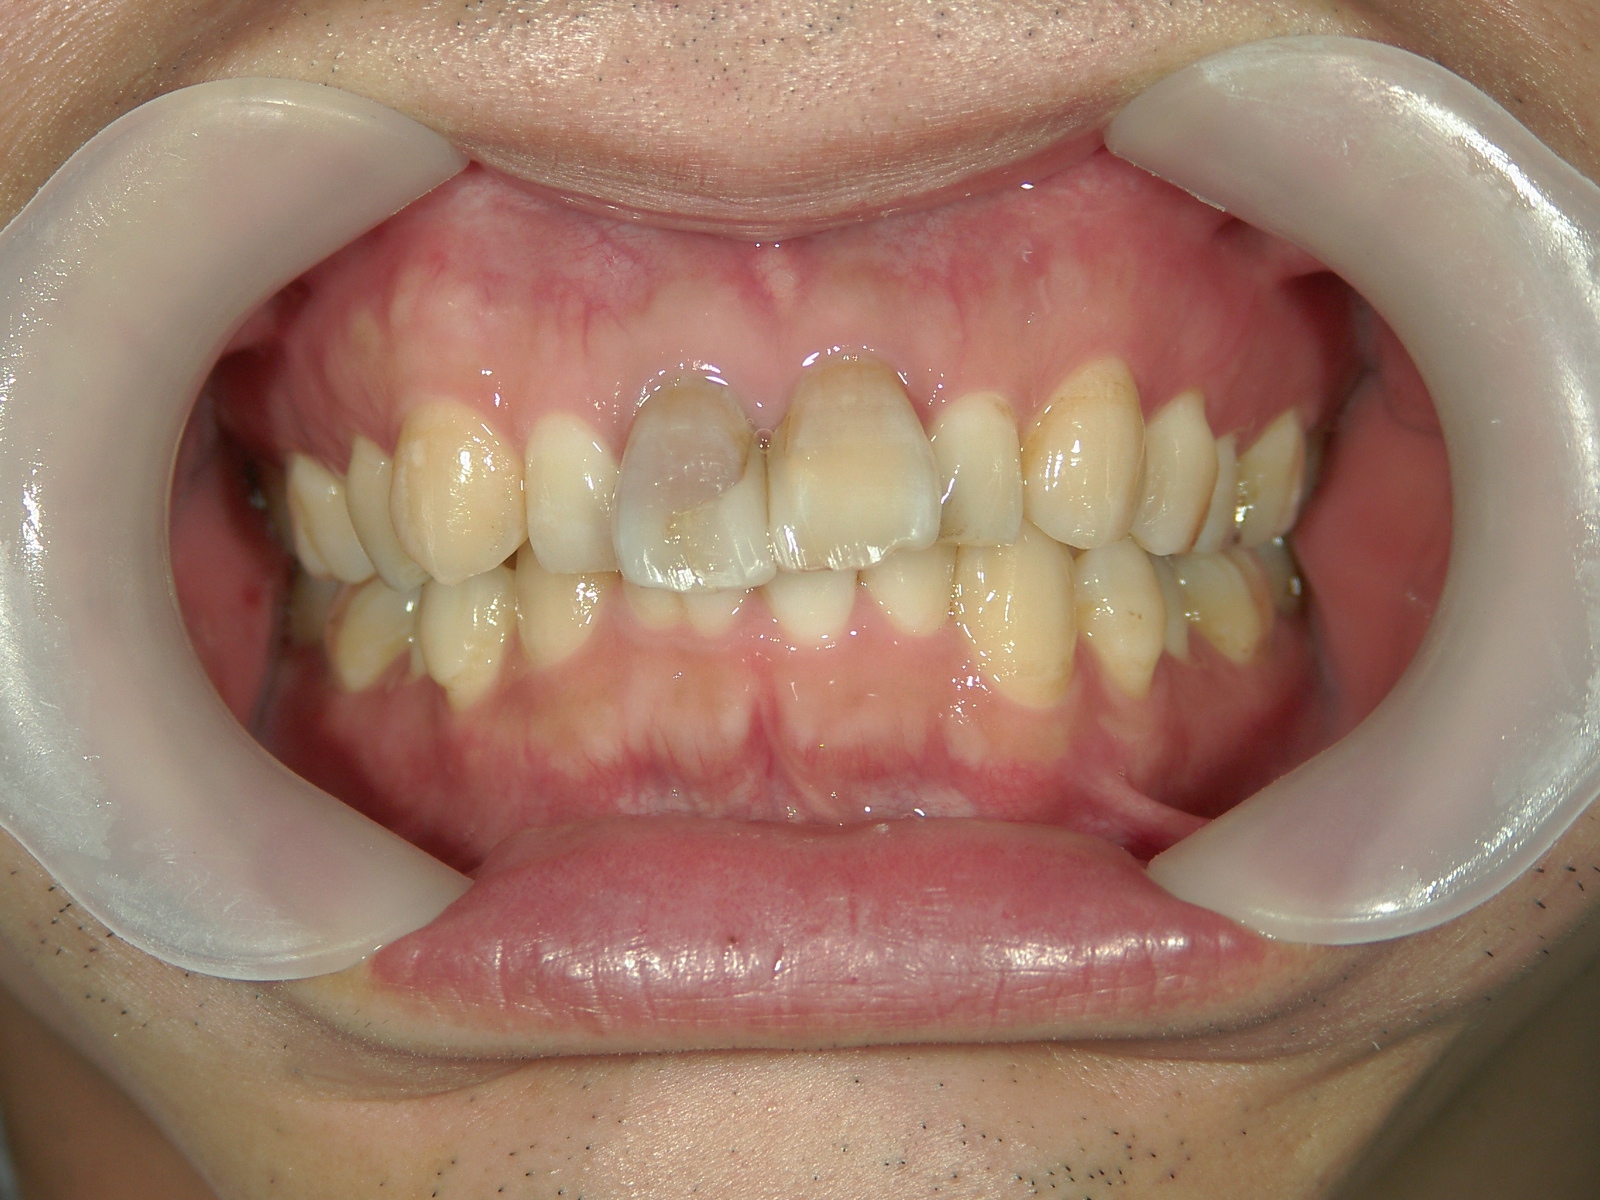

矯正歯科 治療前矯正歯科 治療前

33歳男性 浜松市東区在住

治療期間1年7ヶ月

主訴:前歯の歯並びが気になる。

矯正歯科 治療前 上顎の左右4番計2本を抜歯し叢生を改善。